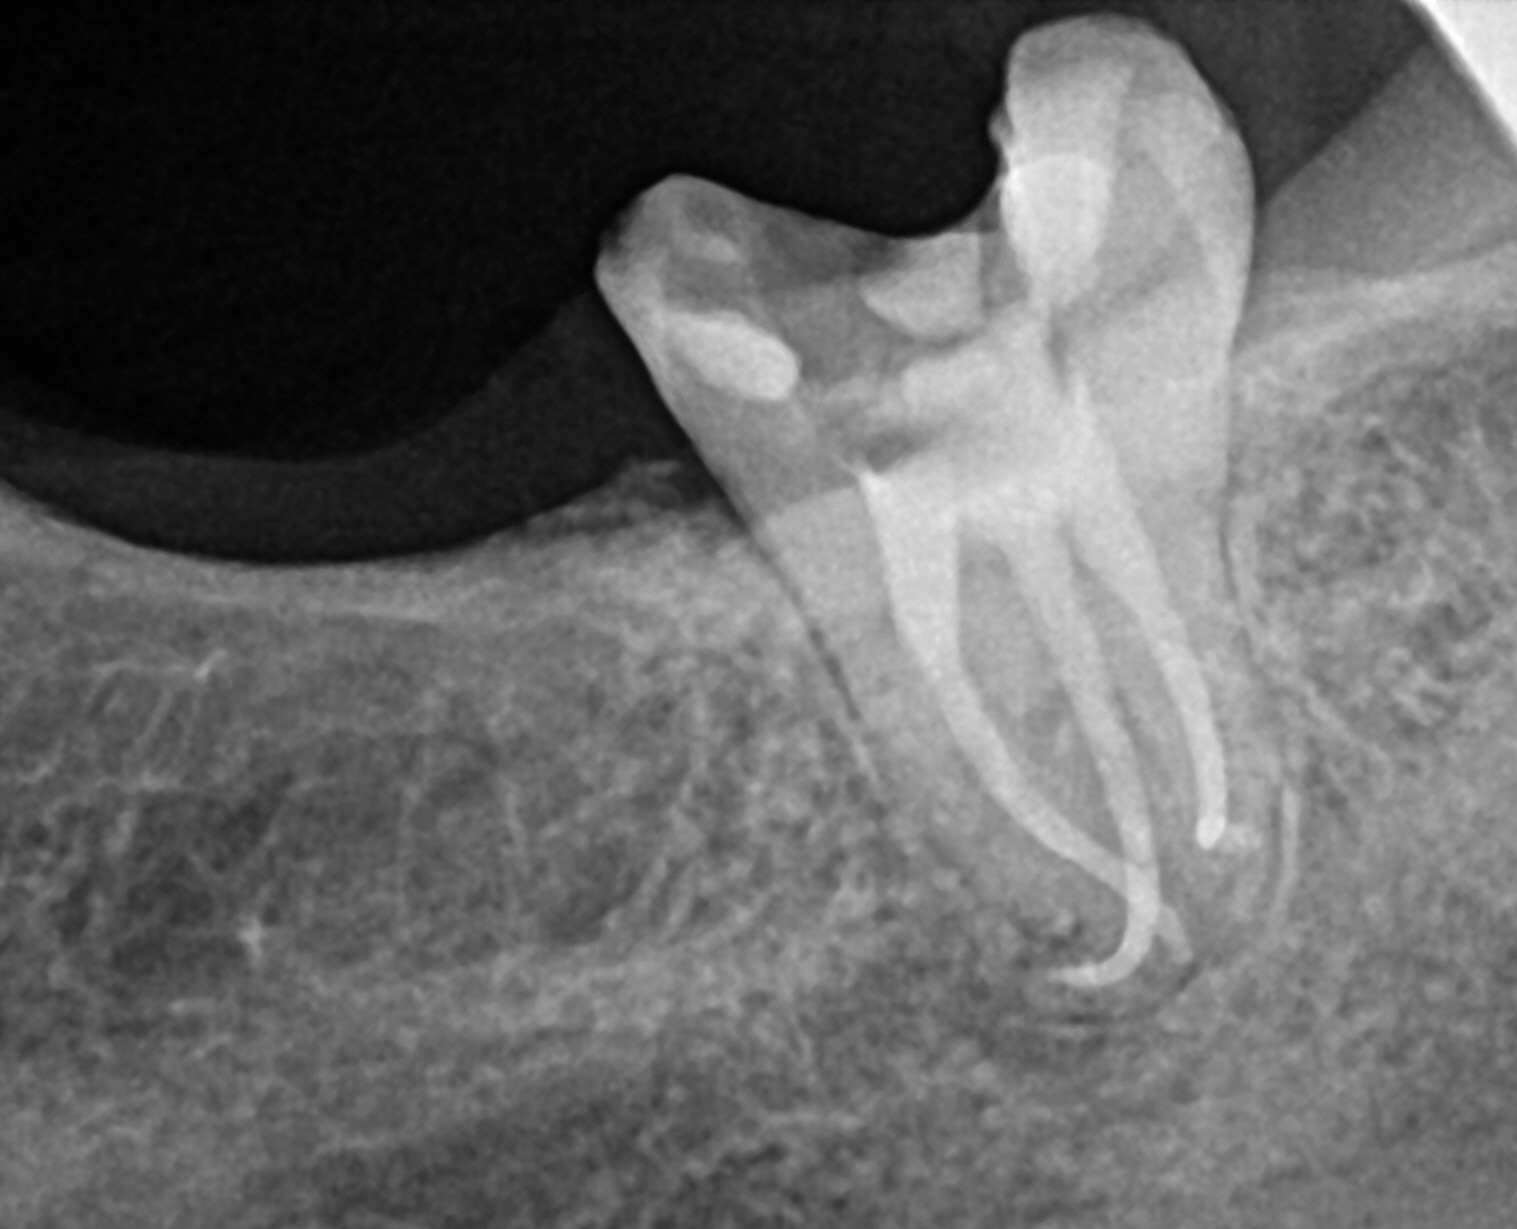

Case 2

This is a retreatment case. The picture on the left shows a lower molar that had been root canal treated many years prior, but either did not heal or at some point afterward became re-infected. The lesion is quite large, extending to the inferior alveolar nerve. While retreating the case Dr Cottle found a previously missed nerve canal (three in one root, five total in this one molar) and was able to disinfect all the canals again. The image on the right shows the completely healed bone one year later.